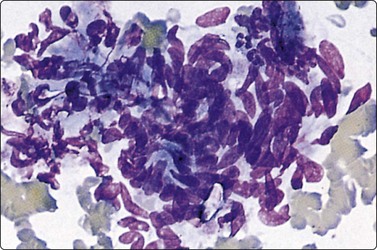

Embryonal carcinoma (Figs 13.33 and 13.34)14,58-61,63,65,66

image image

Fig. 13.33 Embryonal carcinoma

(A) Adenocarcinoma-like tissue fragment of large malignant cells with large vesicular nuclei, coarse chromatin, prominent nucleoli; prominent cytoplasmic vacuolation (MGG, HP); (B) Fragment of undifferentiated mesenchymal tissue right; cluster of malignant epithelial cells with large vesicular nuclei and prominent large nucleoli (H&E, HP) left.

image

Fig.13.34 Embryonal carcinoma

Tissue section corresponding to Fig. 13.33B (H&E, IP).

Criteria for diagnosis

Cell-rich smears,

Frequent three-dimensional clusters,

Occasional tendency to acinar and microglandular grouping,

Large vesicular, obviously malignant nuclei, large nucleoli,

Indistinct cell borders,

Basophilic to amphophilic, sometimes pale, vacuolated cytoplasm,

Immunocytochemistry: cells positive for PLAP, OCT 3/4, CD30, AE1/AE3 and CK7.

The vesicular nuclei of embryonal carcinoma are larger and more pleomorphic than those of seminoma, the chromatin is coarse and irregular and nucleoli are large, occasionally huge, and eosinophilic. The cytoplasm is pale and distinctly vacuolated, but not ‘bubbly’. It is not highly fragile and a TB as in seminoma is not seen. Cytoplasmic boundaries are poorly defined (Fig. 13.33). Hemorrhage and tumor necrosis may be prominent and may hamper the identification of diagnostic cells. It is usually not seen in smears of seminoma. Chromatin threads and reticulated material resembling TB can occur. Large syncytiotrophoblastic cells may be found. Prominent lymphoid/plasma cell infiltrates or mucus are not seen. The presence of cellular mesenchyme on its own does not warrant a designation of teratoma (Figs. 13.33B and 13.34).49